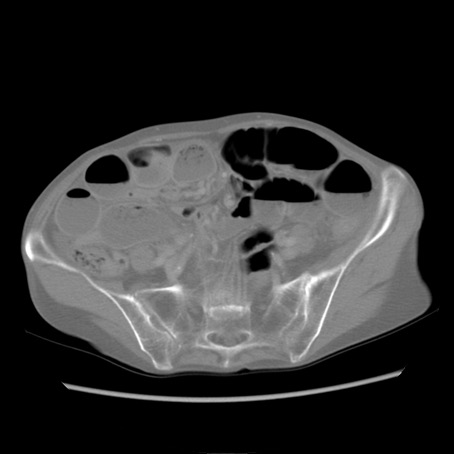

症例25(横断像)

【症例】80歳代女性

【主訴】胸のつかえ感

【現病歴】約9時間前に食後から胸のつかえた感じあり、嘔吐あり、来院。

【既往歴】胃癌(全摘)、胆摘、虫垂炎

【身体所見】心窩部に圧痛あり、反跳痛なし。

【データ】WBC 5700、CRP 0.05